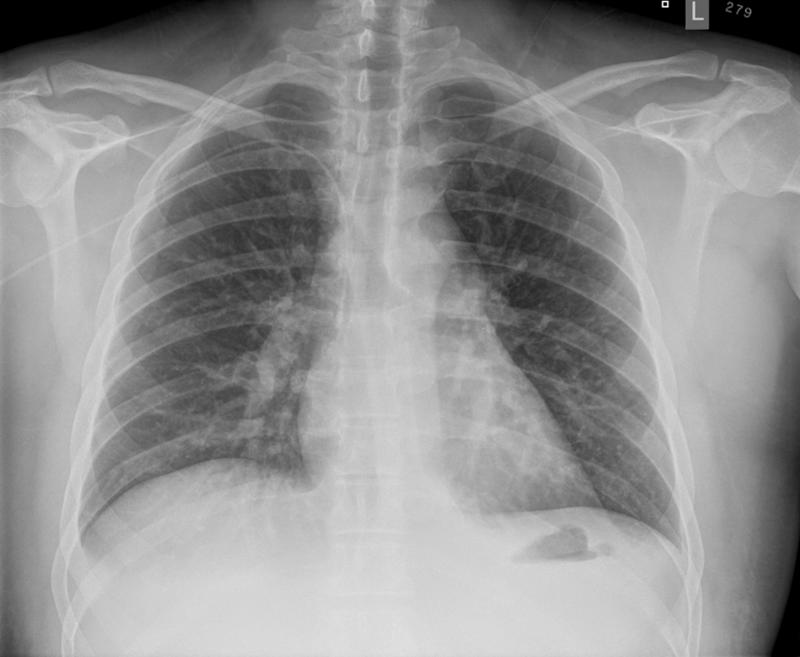

Gallery Mediastinum Lymphoma Lymphoma -Mediastinal and left axillary nodes (see CT)

Lymphoma -Mediastinal and left axillary nodes (see CT)